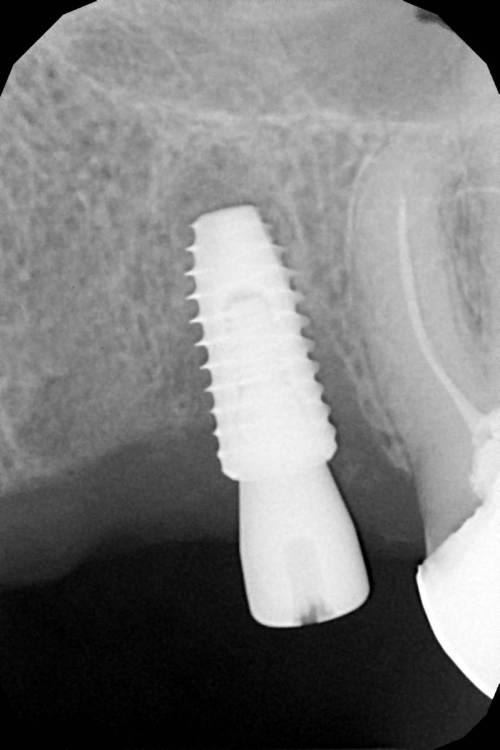

Женька Опубликовано 19 апреля, 2021 Автор Поделиться Опубликовано 19 апреля, 2021 Rg Ссылка на комментарий

Женька Опубликовано 21 июля, 2021 Автор Поделиться Опубликовано 21 июля, 2021 3 месяца минуло... клык на торке 30 неприятные ощущения второй премоляр на 10 и подвижность... отправил на кт. Всё насмарку... Ссылка на комментарий

Борис80 Опубликовано 21 июля, 2021 Поделиться Опубликовано 21 июля, 2021 премоляр в любом случае недозаглубитом болеет... Ссылка на комментарий

Женька Опубликовано 2 августа, 2021 Автор Поделиться Опубликовано 2 августа, 2021 2.5 с тупым перкуторным звуком И вишенка, нет АРБУЗИЩЕ, на торте 2.3 в соседней теме в ортопедии посоветовали перестать уничтожать людям зубы, тоже самое помоему можно сказать и по хирургии... Правильно же понимаю, что протезировать такой (2.3) не стоит. Даже если торк выдержит в 35 чревато проблемами после установки постоянной ортопедии. Ссылка на комментарий